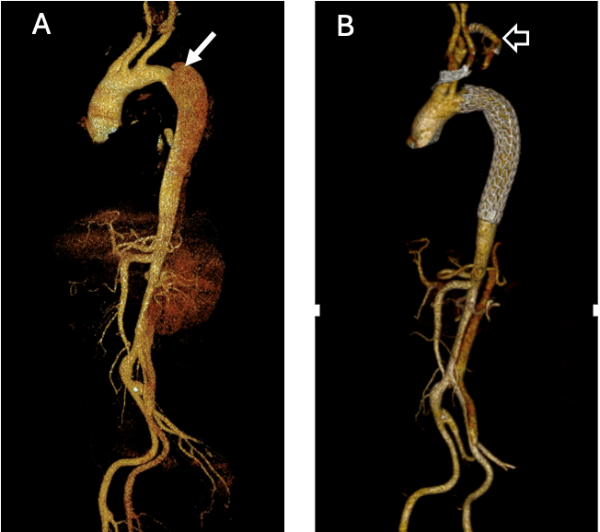

- Endovascular treatment: In dissections of the descending aorta, an endoprosthesis (stent graft) can be placed through a catheter inserted via the groin. This seals the tear in the inner layer of the wall from within, redirecting blood flow into the true lumen and preventing progression of the dissection (Fig. 1).

Fig. 1: A) Dissection of the descending aorta with the entry tear located near the left subclavian artery (white arrow).

B) Endovascular and percutaneous repair with implantation of an endoprosthesis, with a prior bypass between the left carotid and left subclavian arteries (empty white arrow) to allow effective coverage of the entry tear.